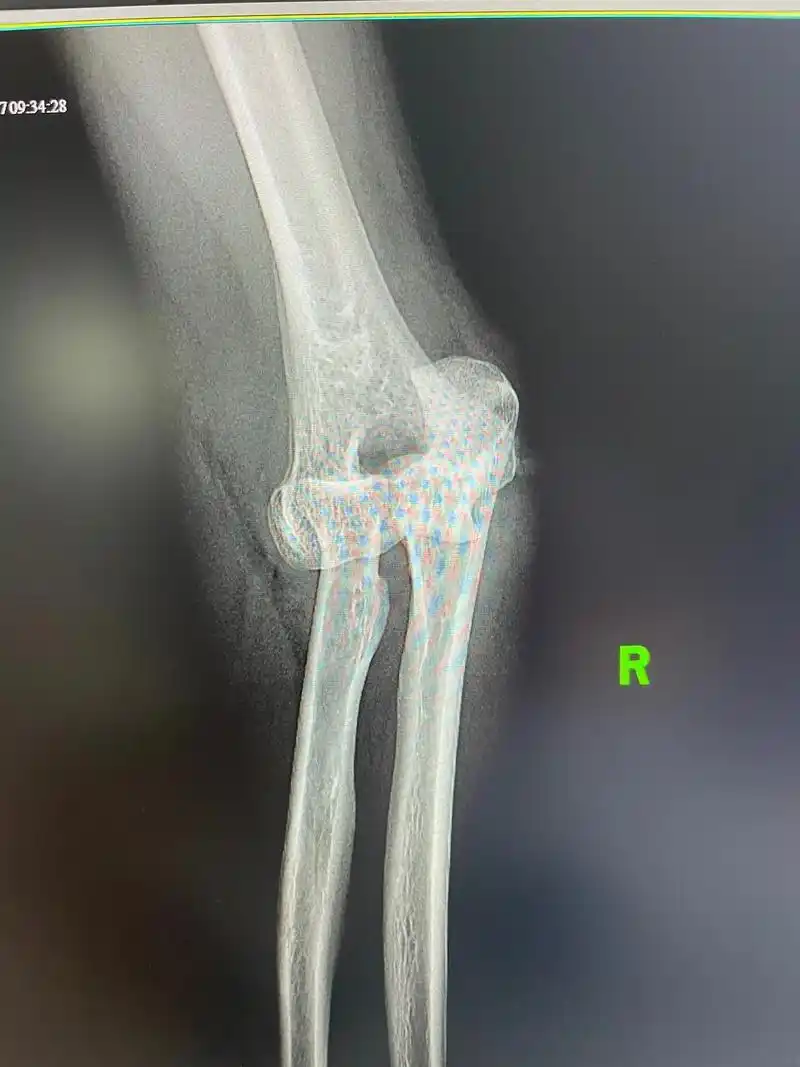

在医学上,桡骨头半脱位手法复位方案有很多种;中医伤科有伸肘牵引前臂

肘关节半脱位复位图解

急性肘关节脱位的6种手法复位方法

医学影像 肘关节脱位,闭合复位.看看还有什么问题? - 抖音